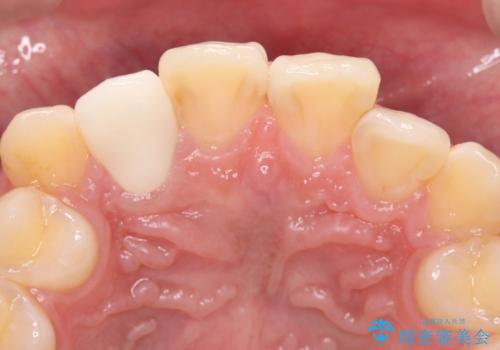

- 主訴:右上の前歯が何しなくても痛い

右上2番の歯に自発痛を認め、症状や歯髄診・レントゲン像から不可逆性歯髄炎と診断し、精密根管治療から歯冠補綴まで行うこととなりました。

初診時に歯髄診断を行い、不可逆性歯髄炎と診断し抜髄から補綴修復までの流れを説明し、精密根管治療、ファイバ-コア築造、オールセラミッククラウン(St)修復を行うこととしました。